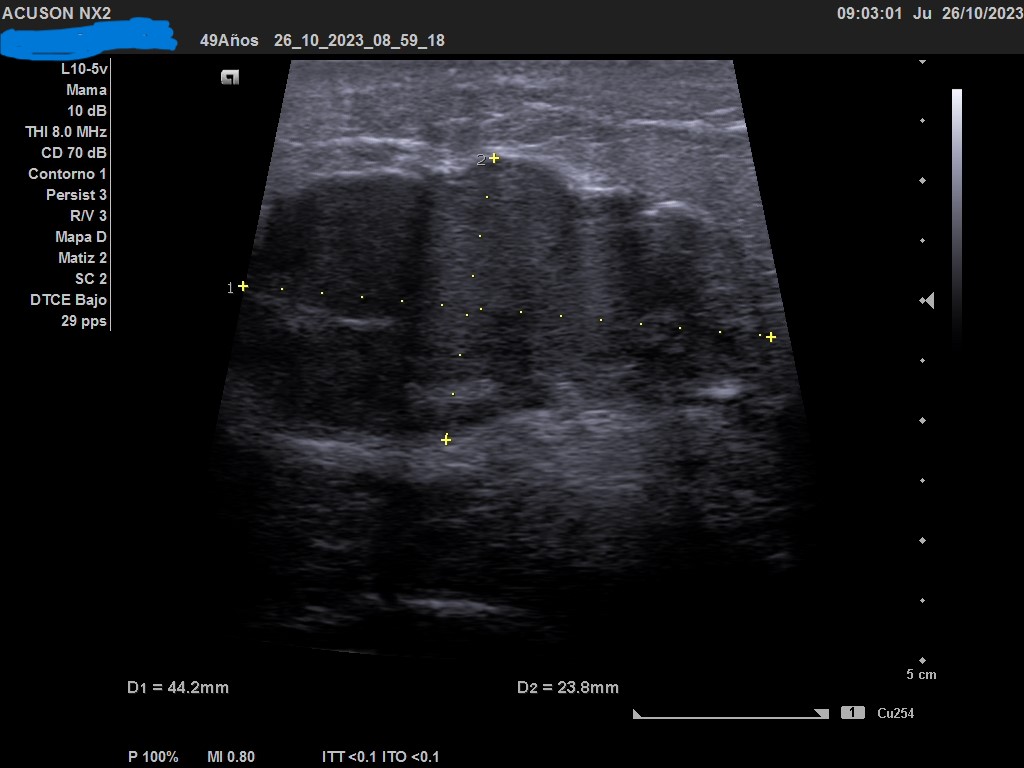

Hallazgos ecográficos

Ecografía: mama izquierda se observa tumoración hipoecogénica lobulada en cuadrante superior externo de aproximadamente 4 cm, heterogénea, que capta al Doppler color y dos adenopatías de aspecto reactivo en axila homolateral. Imagen sospechosa de malignidad.

Ecografía de mama hospitalaria: Se confirma en mama izquierda masa sólida palpable de al menos 56 mm, de contorno mal definido, sospechosa de malignidad. Se realizará BAG ecoguíada, y adenopatías axilares izquierda de aspectos patológico. PAAF de ganglio izquierdo dirigida por ecografía: Citología positiva para malignidad. Compatible con metástasis de carcinoma. Biopsia BA Tipo histológico: Carcinoma infiltrante. Grado histológico: Grado III, pobremente diferenciado.